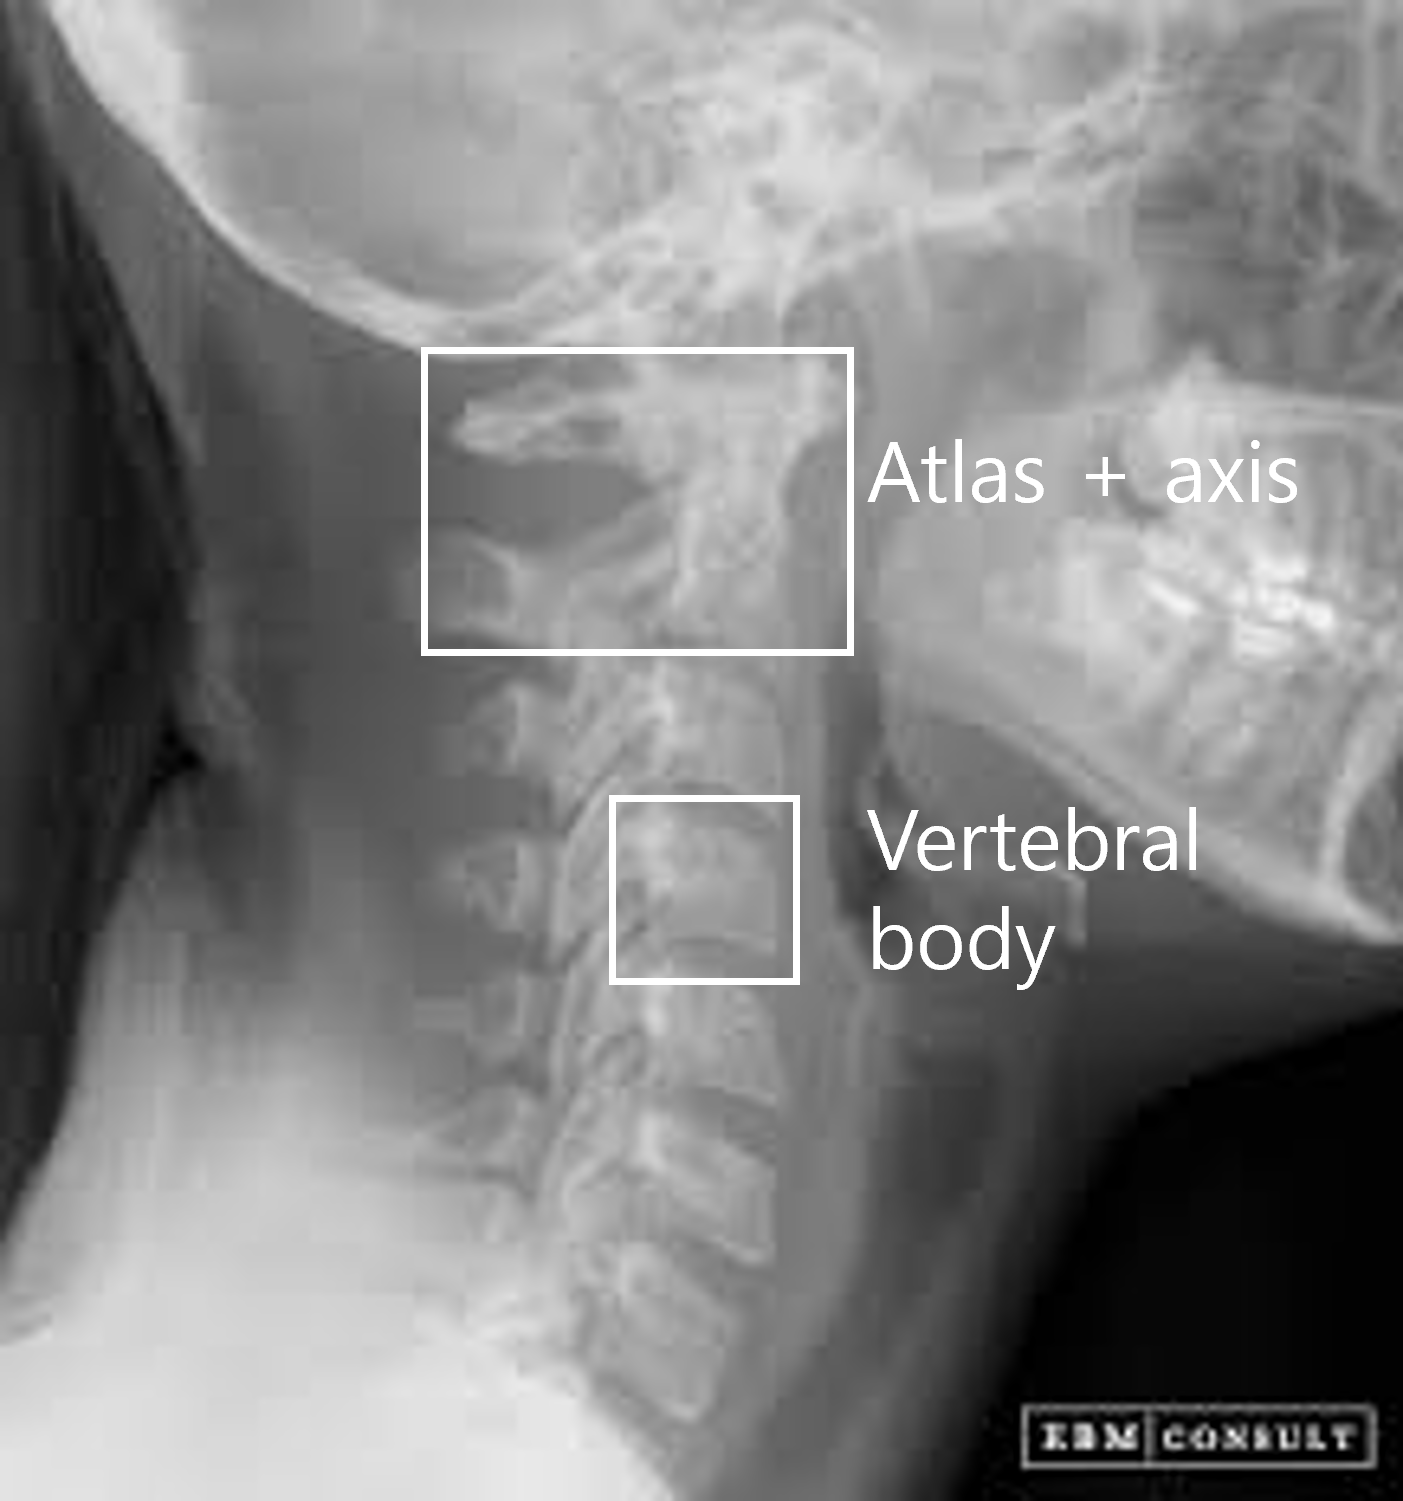

AI 모델이 의료 영상을 효과적으로 학습할 수 있도록, 각 부위와 촬영 방식(AP, Lateral 등)에 맞추어 세그멘테이션(Segmentation), 키포인트(Keypoint), 바운딩 박스(Bounding box) 등 세 가지 방식의 정밀 라벨링 작업을 복합적으로 수행했습니다.

고관절(Hip) 및 무릎(Knee): 대퇴 근위부와 비구 등의 세그멘테이션, tear drop 및 대퇴 골두를 포함한 다수의 키포인트 검출 작업을 진행했습니다.

어깨(Shoulder) 및 손목(Wrist): 상완골(humerus), 견봉(acromion), 주상골(scaphoid) 등 구조물을 분할하는 다중 클래스 세그멘테이션(Multi class Segmentation)과 세부 좌표를 지정했습니다.